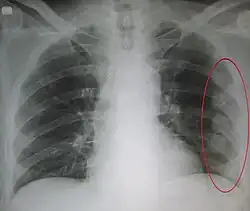

![]() | |

| An X ray showing multiple old fractured ribs of the person's left side as marked by the oval | |

-

Right sided pneumothorax and rib fractures -